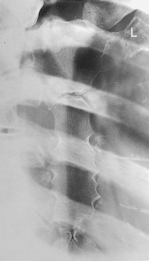

Fig. 7-13 45° RAO above diaphragm—bilateral, right anterior injury (to shift spine away from injury).

• Oblique 45°, rotate spine away from area of interest

• Involved region of thorax is centered to IR with top of IR ≈4 cm (1.5″) above shoulders